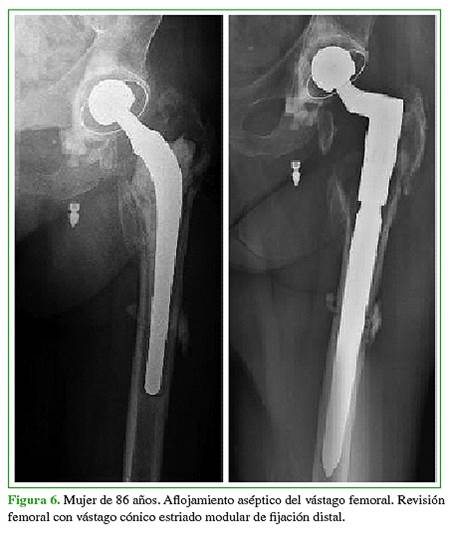

Al final del seguimiento, el 95,05% de los pacientes incluidos en esta serie tenía implantes estables sin que fuera necesaria una nueva revisión (Figuras 6 y 7).